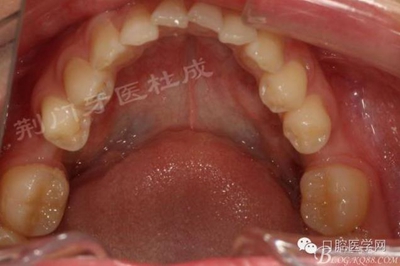

術(shù)前口內(nèi)照片:

檢查:16齲壞穿髓,探(-)叩(+++),無(wú)松動(dòng),36 46 缺失,37 47 近中傾斜嚴(yán)重,44畸形中央尖牙體變色,叩(+),溫度測(cè)試無(wú)反應(yīng) ,18 28 38 48 萌出牙體偏頰